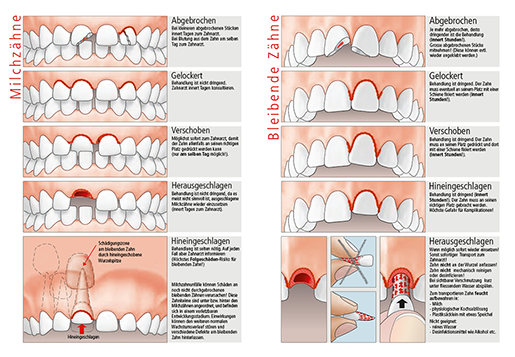

Zahn ist gelockert

Zahn ist verschoben

Zahn ist hineingeschlagen

Belassen Sie den Zahn in Position und suchen Sie umgehend Ihren Zahnarzt auf.

Behandlung ist dringend. Der Zahn muss eventuell an seinem Platz mit einer Schiene fixiert werden (innert Stunden!).

Zahn ist abgebrochen

Versuchen Sie das abgebrochene Stück zu finden!

Wenn die Möglichkeit gegeben ist, probiert der Zahnarzt dieses wieder anzukleben.

Je mehr abgebrochen, desto dringender ist die Behandlung (innert Stunden!).

- Das abgebrochene Zahnstück wird gefunden

Bewahren Sie dieses feucht auf und gehen Sie damit zu Ihrem Zahnarzt.

( ...mit etwas Speichel vom Patienten in einer Frischhaltefolie oder in ein Plastiksäcklein, bestenfalls in einer Zahnrettungsbox)

- Das abgebrochene Zahnstück ist nicht aufzufinden

Falls keine Schmerzen bestehen kann der Zahnarzt auch noch am folgenden Werktag aufgesucht werden.

Zahn ist herausgeschlagen

Wenn möglich sofort wieder einsetzen!

Sonst sofortiger Transport zum Zahnarzt!

Behandlung innert Stunden nötig!

Bewahren Sie den ausgeschlagenen Zahn in einer Zahnrettungsbox auf (...erhältlich bei Ihrer Apotheke oder bei einer Notapotheke).

Alternativ eignet sich kühle H-Milch oder wickeln Sie den Zahn mit etwas Speichel vom Patienten in einer Frischhaltefolie oder in ein Plastiksäcklein.

Suchen Sie sofort Ihren Zahnarzt auf und bringen Sie den ausgeschlagenen Zahn mit.

Wichtig:

- Zahn nicht an der Wurzel anfassen!

- Niemals den Zahn reinigen oder trocknen!

- Bei sichtbarer Verschmutzung nur kurz unter fliessendem Wasser abspülen.

- Zahn nicht mechanisch reinigen oder desinfizieren!

- Zum transportieren Zahn feucht aufbewahren!

Nicht geeignet sind:

- Desinfektionsmittel wie Alkohol etc.